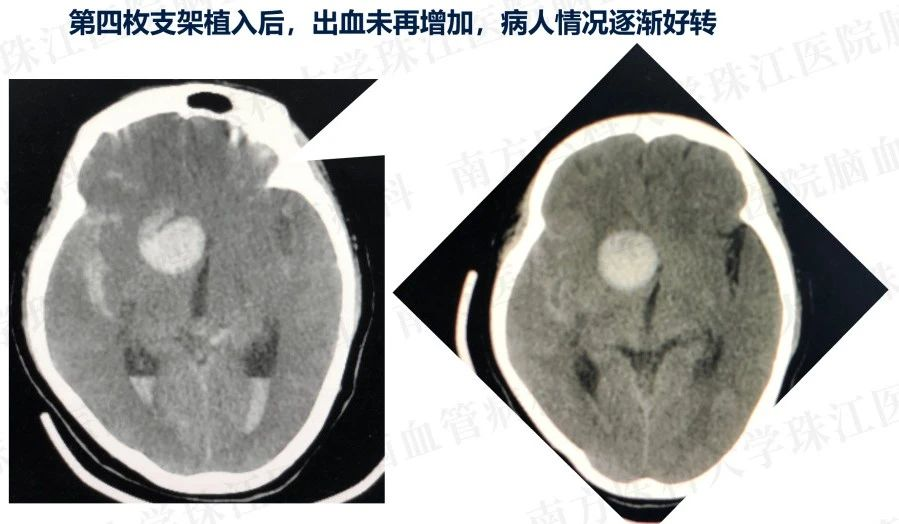

患者入院后造影发现“颈内动脉床突上段巨大动脉瘤,大小约2.7x3.5cm。决定行PIPELINES密网支架植入治疗。

患者入院后造影发现“颈内动脉床突上段巨大动脉瘤,大小约2.7x3.5cm。决定行PIPELINES密网支架植入治疗。